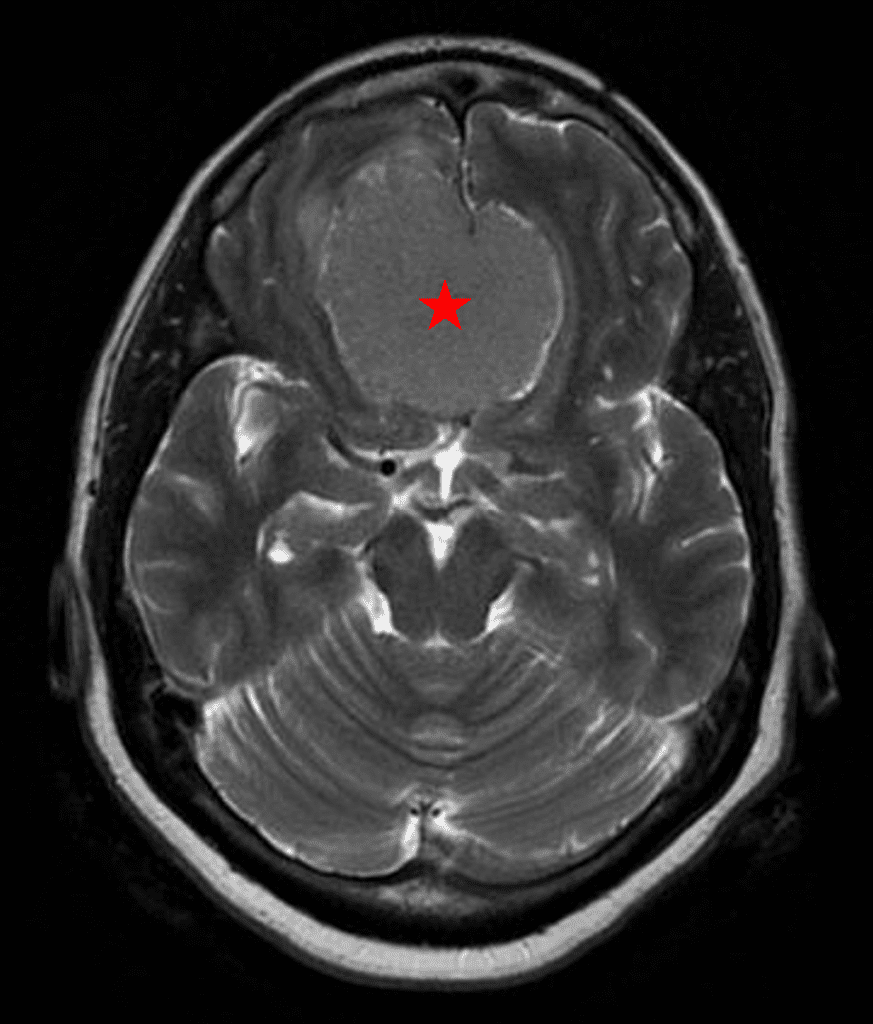

Figure 2a – Preoperative MRI demonstrating an extra-axial lesion with surrounding vasogenic edema and mass effect on the frontal lobes.

Figure 2b – Postoperative MRI demonstrating resolution of mass effect.

She was started on high-dose steroid and antiseizure prophylactic medicine. Surgical intervention was offered for mass effect, symptomatic relief, neurologic preservation, and histopathologic diagnosis. Dr. Gaudin performed a bifrontal craniotomy with complete resection of neoplasm through an interhemispheric and subfrontal approach. Postoperative imaging demonstrated a gross total resection without residual tumor and resolution of mass effect (Figure 1b and 2b). Intraoperative pathology was consistent with meningioma, WHO grade 1. She recovered very well, and was discharged home on postoperative day 3. On her follow-up outpatient visit, her preoperative symptoms had fully resolved, and her olfactory sense was maintained.